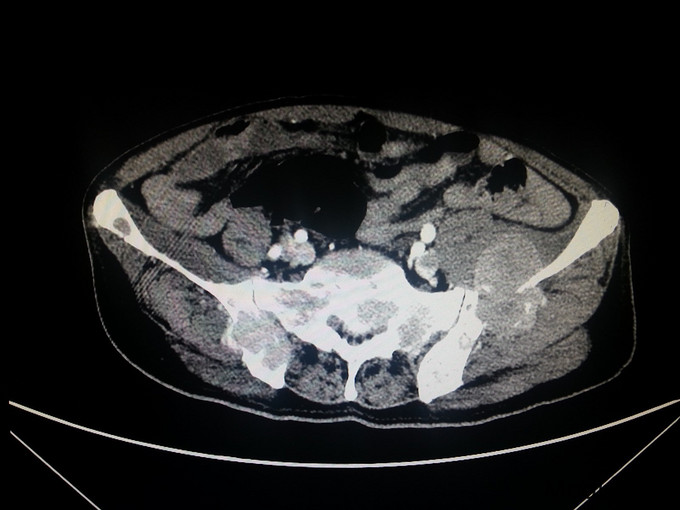

患者,男,68岁,因门诊CT检查发现前列腺肿瘤、骨转移入院

前列腺穿刺病理 :前列腺癌 Gleason4+4 PSA>100ng/ml fPSA>30ng/ml

患者入院后经会阴前列腺穿刺活检,病理诊断为前列腺癌 Gleason4+4 ;予以口服氟他胺以及静脉注射唑来膦酸、戈舍瑞林缓释剂皮下注射治疗; 治疗半年后复查 CT提示前列腺肿瘤缩小;PSA45ng/ml;患者一般情况明显好转